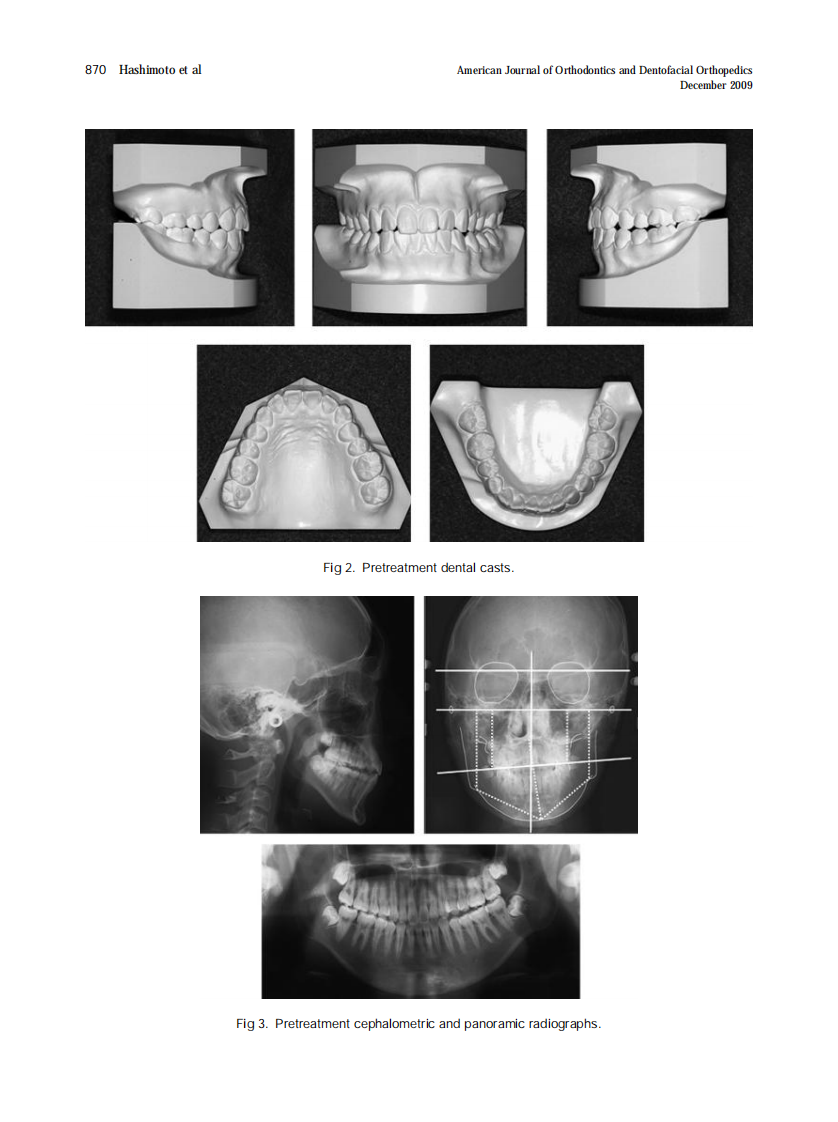

AJO-DO

2009_136_6_37.pdf